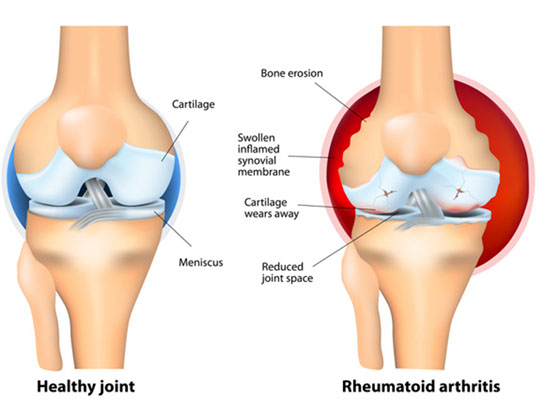

Rheumatoid arthritis

Morning stiffness that lasts >30 min and improves c use

*** in RA morning stiffness lasts a Really long time***

- symmetric synovial joint involvement and systemic symptoms

-- synovial fluid studies show: dec viscosity, dec C3, inc WBCs

Type III Hypersensitivity

~80% have positive rheumatoid factor (anti-IgG ab)

-- synovial cells express an antigen that cross-reacts c B-cell receptors stimulating B-cells to become plasma cells and produce RF (an ab that binds the Fc of IgG)

- anti-CCP ab less sensitive but more specific

-- strongly assoc c HLA-DR4

Features:

Pannus is granulomatous tissue rich in inflam cells and fibroblasts in joint space that proliferates and releases cytokines (TNF-a and IL-1) causing a cell-mediated destruction of articular cartilage and eventual ankylosis (a type IV HS)

- Carpal tunnel from flexor-tenosynovitis or median n compression from swelling

-- Rheumatoid synovitis on micro shows villous formation, hyperplasia/hypertrophy of the lining cells, fibrinoid necrosis and chronic inflam in the synovial membrane (tx'd surgically c physiotx)

Atlantoaxial joint subluxation

Subcutaneous rheumatoid nodules

Ulnar deviation (No DIP involvement)

Swan neck deformity

Ischemic strokes

Caplan's and Felty's syndromes

Pleuritis c pleural effusion, carditis, vasculitis, atherosclerosis

Baker's cysts behind the knees

Anemia of chronic dz (dec Fe and TIBC, inc ferritin)

Rice bodies - free-floating fragments of synovium and cartilage in the joint space

Rheumatoid subcutaneous nodules - Occur in ¼ affected individuals, usually in areas subjected to pressure; in elbow, forearm, occiput

- Central necrosis rimmed by palisading histiocytes

- MCC death: coronary artery dz

Tx: NSAIDS, DMARDS, TNF-a inhibitors, leflunomide, rituximab